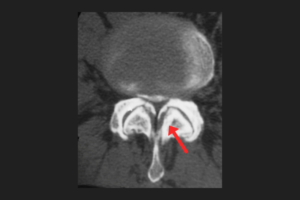

Bacaklarda uyuşma, sinirleri, kasları veya omuriliği etkileyen birçok hastalığın belirtisi olabilir. Merkezi sinir sistemi tümörleri (beyin tümörü, omurilik tümörü, omuriliğe baskı yapan omurga tümörü), bel fıtığı, sırt fıtığı, belde kanal daralması gibi dejeneratif hastalıklar uyuşmaya yol açabilir. Siyatik sinir sıkışması ve basıya uğraması da bacaklarda uyuşma ve karıncalanma hissine neden olabilir. Bunun yanı sıra, bel kayması, diyabet, multiple skleroz (MS), vitamin eksiklikleri (özellikle B12 eksikliği), dolaşım bozuklukları ve bazı nörolojik hastalıklar da bacak uyuşmasına sebep olabilir.

Bacakta uyuşma ve karıncalanma genellikle sinir sıkışmaları veya sinirlerin tahriş olması sonucu ortaya çıkar. Özellikle bel fıtığında, siyatik sinir sıkışmasında ve farlateral disk hernilerinde bacakta yanma, karıncalanma ve uyuşma hissi olabilir. Dolaşım bozuklukları da bacaklarda uyuşmaya yol açabilir.

Bacak uyuşması durumunda beyin ve sinir cerrahisi (nöroşirürji) veya nöroloji uzmanına başvurulmalıdır. Tanı için MR, tomografi, EMG gibi tetkikler yapılmalıdır. Eğer sorun damarlarla ilgiliyse kalp-damar cerrahisi uzmanına yönlendirme yapılabilir.